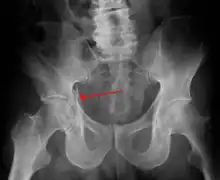

Acetabular fracture as seen on plain X-ray

To understand the fracture pattern of a fractured acetabulum, it is essential to have minimum three x-ray views, though use of CT scan with 3-D reconstruction of images has made understanding of these fractures easier.

1. Pelvis with both hips antero posterior view. This view shows six important landmarks of the acetabulum, specifically: